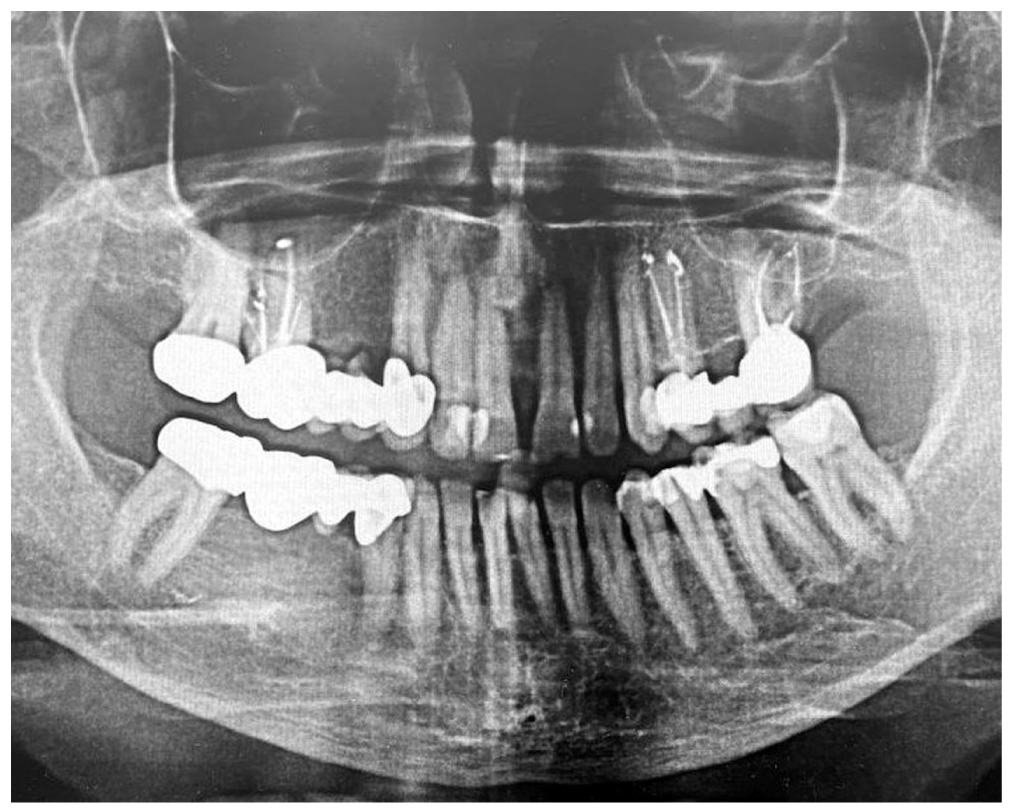

Three disease stages are known — mild, moderate and severe. The mild degree of severity is characterized by the presence of swelling, cyanotic and bleeding mucosa of the gingival margin, 1st degree loosening of teeth and by the presence of a periodontal recess up to 4 mm deep. The radiology images in cases of mild disease show dilation of periodontal fissure, loss of integrity in the cortical plate, resorption of the alveolar bone walls by 1/3 of the dental root length. In cases of moderate severity of chronic generalized periodontitis, the findings include an increase in the depth of periodontal recess up to 6 mm, pathological loosening of teeth (2nd degree) and exposition of the dental roots. The orthopantomograms from the patients with 2nd degree show resorption of alveolar bone walls, reaching up to 1/2 of the length of the dental root and showing signs of destruction in the cortical plate. The severe chronic generalized periodontitis is characterized by an increase in the pathological loosening of teeth (up to degree II or III), by dislocation of teeth, by the presence of periodontal recesses with a depth of more than 6 mm and with the presence of purulent exudate, by significant traumatic occlusion and exposition of the roots. Upon radiology examination, the findings include resorption of alveolar bone walls to a distance of more than 1/2 of the dental root length with the presence of pathological bone pockets.

During the analysis of the obtained data, the highest concentration of T. forsythia was found in patients from Group 3 — 6.6±1.87 GE, which is 1.3 times higher comparing to the values in Group 1 (p <0.001), 1.16 times higher comparing to Group 2 and 2 times higher comparing to the values in the control group. In patients from Group 3, the clinical signs and visual examination results have revealed a degree 2–3 pathological loosening of teeth, dislocation of teeth, as well as the presence of periodontal recesses with a depth exceeding 6 mm together with the presence of purulent exudate, significant traumatic occlusion and exposed roots. Upon radiology examination, this category of patients shows resorption of alveolar bone walls exceeding 1/2 of the length of dental roots along with the presence of pathological bone pockets (Fig. 4).

Fig. 4. Orthopantomogram — patient G., aged 56 years old: severe chronic generalized periodontitis.